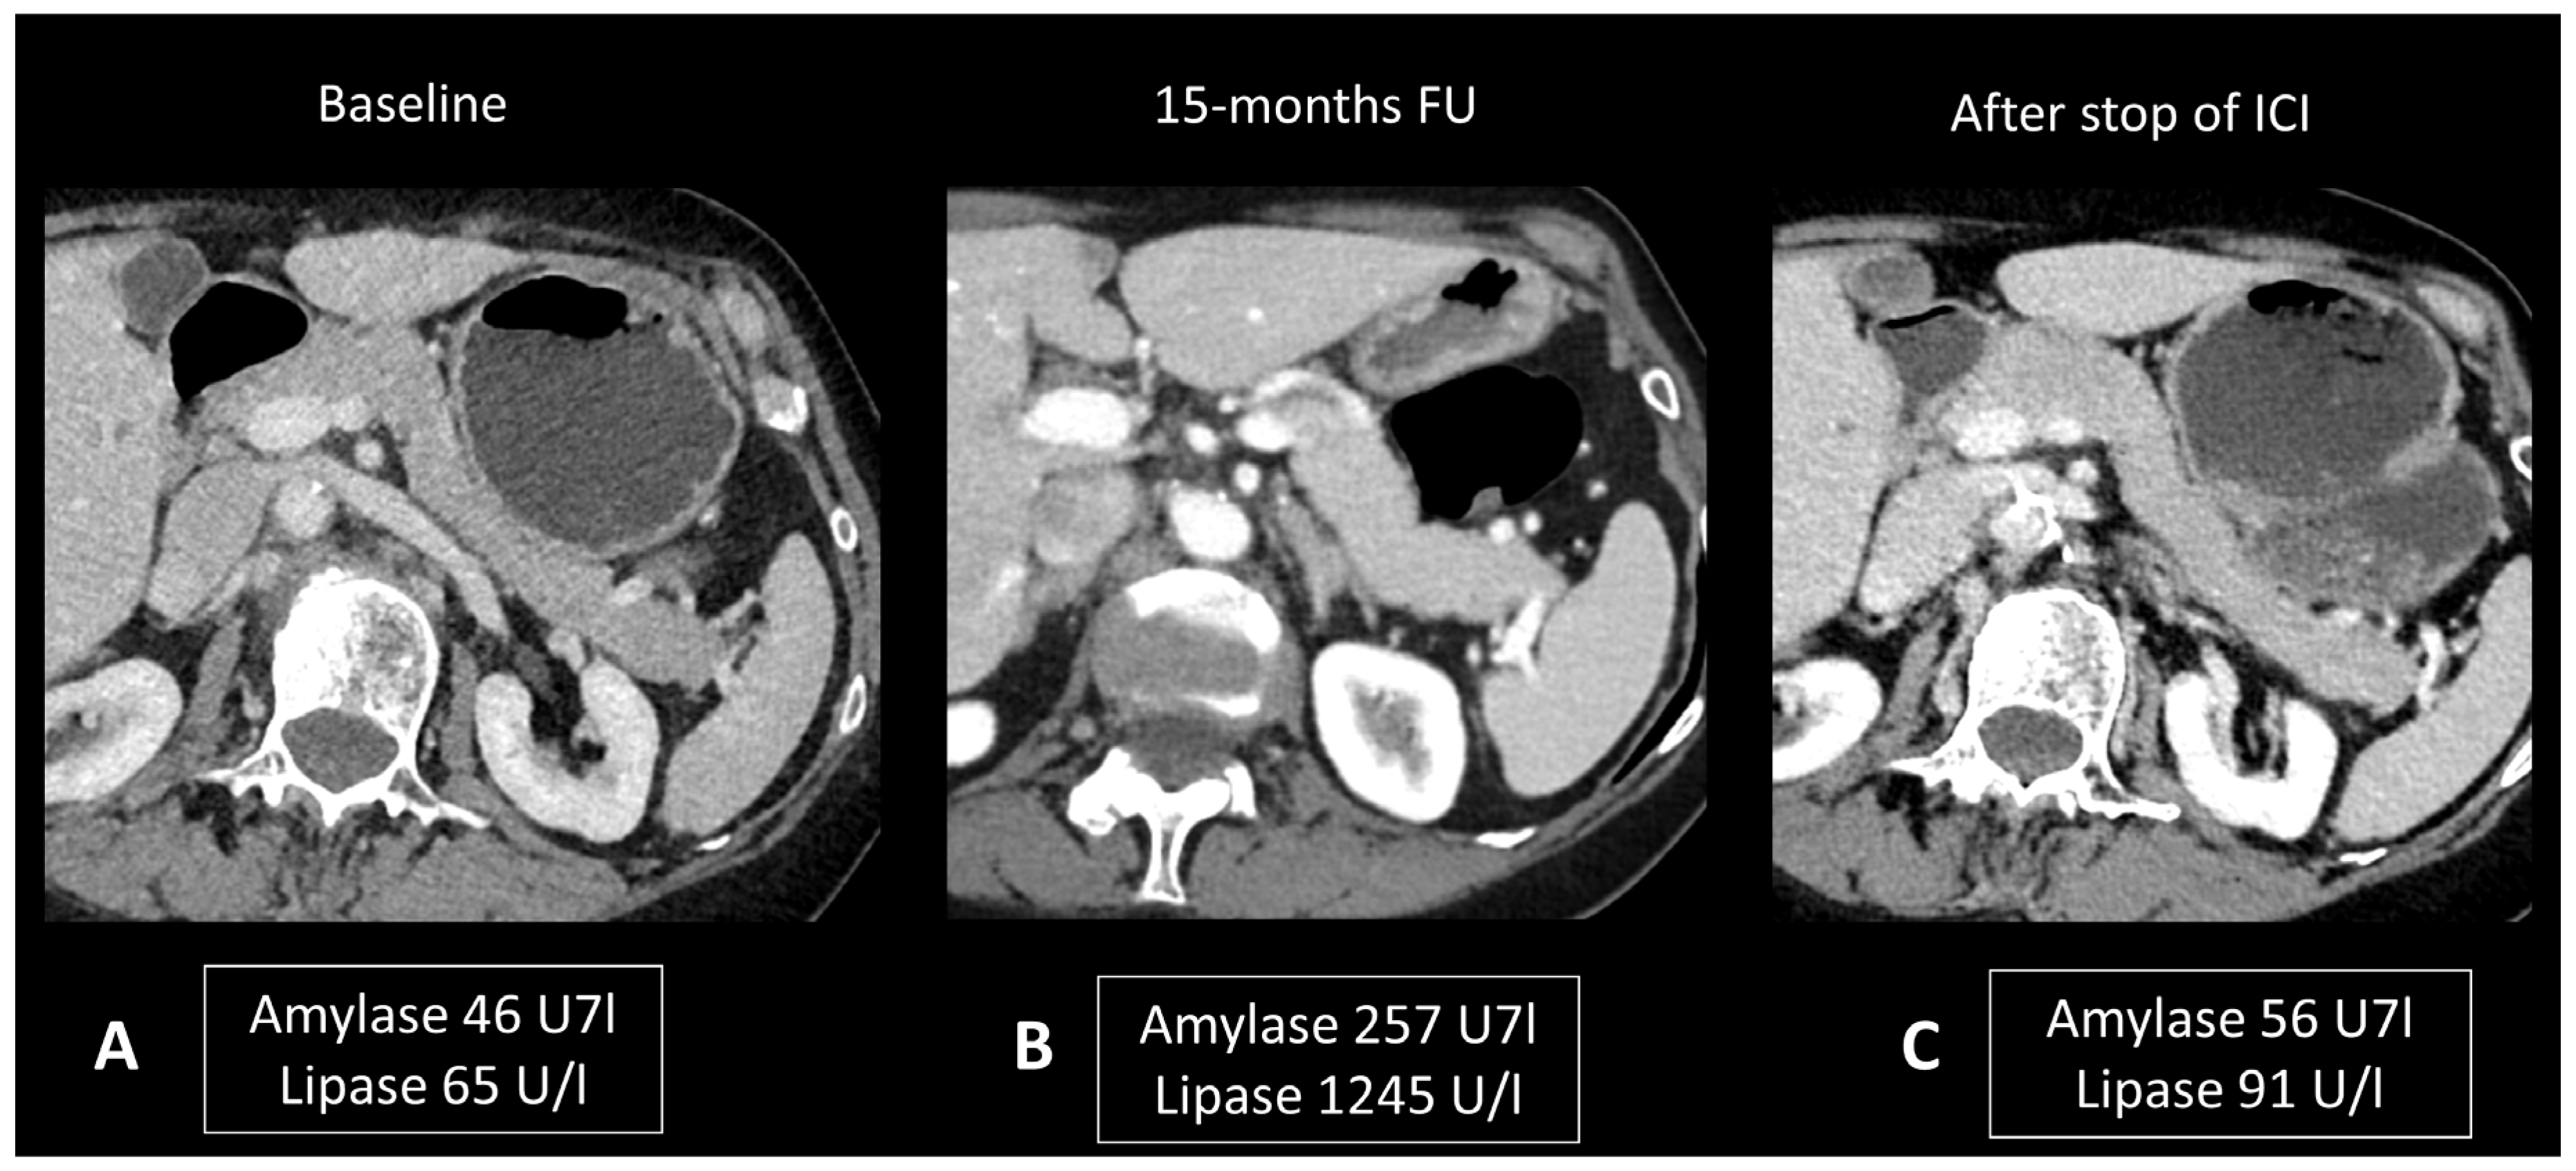

2.4.2. Ir-Pancreatitis

- Abu-Sbeih, H.; Tang, T.; Lu, Y.; Thirumurthi, S.; Altan, M.; Jazaeri, A.A.; Dadu, R.; Coronel, E.; Wang, Y. Clinical characteristics and outcomes of immune checkpoint inhibitor-induced pancreatic injury. J. Immunother. Cancer 2019, 7, 31. [Google Scholar] [CrossRef] [PubMed]

- Das, J.P.; Postow, M.A.; Friedman, C.F.; Do, R.K.; Halpenny, D.F. Imaging findings of immune checkpoint inhibitor associated pancreatitis. Eur. J. Radiol. 2020, 131, 109250. [Google Scholar] [CrossRef] [PubMed]